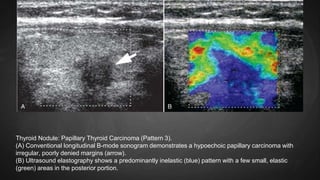

Thyroid Nodule: Papillary Thyroid Carcinoma (Pattern 3).

(A) Conventional longitudinal B-mode sonogram demonstrates a hypoechoic papillary carcinoma with

irregular, poorly denied margins (arrow).

(B) Ultrasound elastography shows a predominantly inelastic (blue) pattern with a few small, elastic

(green) areas in the posterior portion.